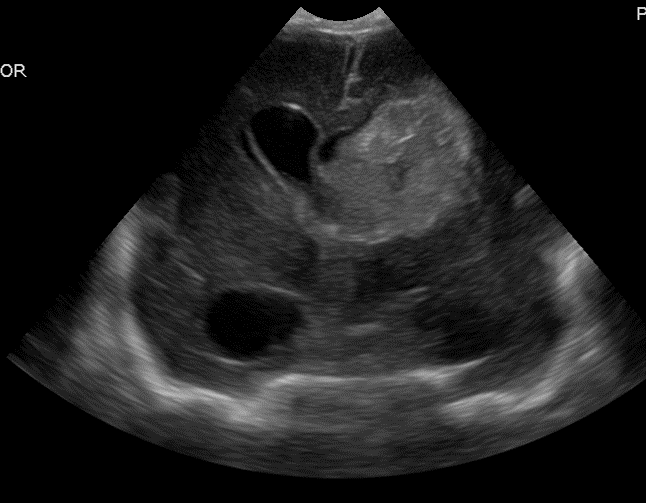

Info Images Findings Impression Reco/Acuity Case Images View Images / Launch Visage Case Notes History Full term infant. We are asked to evaluate posterior fossa cyst. Exam Gray scale and Doppler Ultrasonographic examination of the head. Prior Study N/A Dicom View Reference Material

Section 1 Submit Findings Case149 Findings Brain The brain is immature. Yes No There is under-sulcation and open sylvian fissures. Yes No There is/are multiple hypoechoic areas in the periventricular white matter. Yes No There is/are multiple hyperechoic areas in the periventricular white matter. Yes No There is diffuse cerebral edema with diffusely increased echogenicity of the brain parenchyma and loss of grey white matter differentiation. Yes No The thalami/basal ganglia are hypoechoic. Yes No There is periventricular calcification. Yes No There is intra-parenchymal calcification. Yes No CSF spaces/ventricular system There is a prominence of the extra axial fluid spaces. Yes No There are debris/septations in the extra axial fluid spaces. Yes No There are debris/septations in the ventricles. Yes No There is a subdural collection on the right/left side. Yes No There is prominence of the ventricular system. Yes No There is an asymmetry of the ventricular system. Yes No There is a cavum septum pellucidum. Yes No There is a midline shift towards right/left. Yes No The choroid plexus is bulky/lobulated. Yes No There is a choroid plexus cyst measuring… Yes No There are debris/clots in the occipital horn. Yes No There is a posterior fossa cyst measuring… Yes No The tentorium is elevated/depressed. Yes No The lateral ventricle/s are dilated. Yes No The third ventricle is dilated. Yes No The 4th ventricle is dilated. Yes No There are pseudo cysts. Yes No Germinal matrix hemorrhage (Only in the premature infants): Please do not answer if the patient is a full term. There is a germinal matrix hemorrhage, consistent with a grade I hemorrhage. Yes No There is an intraventricular extension consistent with a grade II hemorrhage. Yes No There is an intraventricular extension with the dilatation of ventricles, consistent with a grade III hemorrhage. Yes No There is an intra-parenchymal extension, consistent with grade IV hemorrhage. Yes No On color Doppler examination, the Resistive index in the anterior cerebral artery is… There is a loss of the diastolic flow on the Doppler exam. Yes No There is altered vascularity on Doppler imaging. Yes No There is an AVM in the region of… Yes No